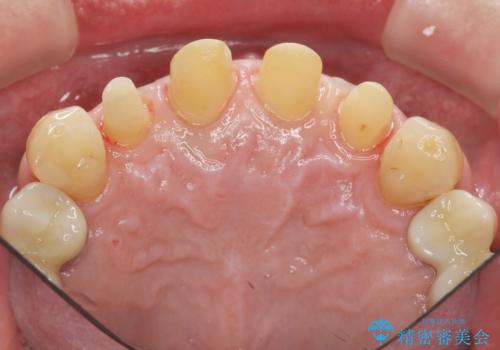

虫歯のマイクロスコープによる丁寧な除去、根管治療、深い虫歯に対する挺出(エクストリュージョン)および歯周外科を行ったのち精度の高いセラミッククラウン製作治療を計画します。

虫歯の放置により、根管治療や深い虫歯に対する処置が必要になりましたが丁寧に一つづつ処置を行ったことで抜歯をすることなく歯を残すことができました。

セラミッククラウンの製作をする前に、歯内・歯周環境の整備は非常に大切です。